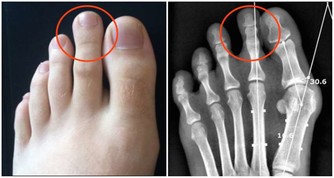

4.骨科醫生:吃補鈣藥不如吃含鈣食物

食補比藥補更有效用,真的想要改善自己的骨骼健康,日常的飲食就要做起,

成年人每天適宜攝取800毫克的鈣量,這些都可以從食物中取得,

像是芝麻、海帶、蝦皮、牛奶、乳酪、芥菜、海參和豆製品等等,

飲食配上運動才是身體健康的不二法門。